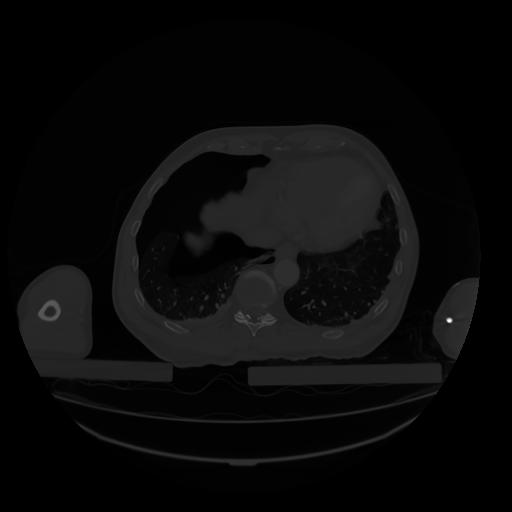

28 CUERPO,CE,Vol,2.0,CUERPO,,